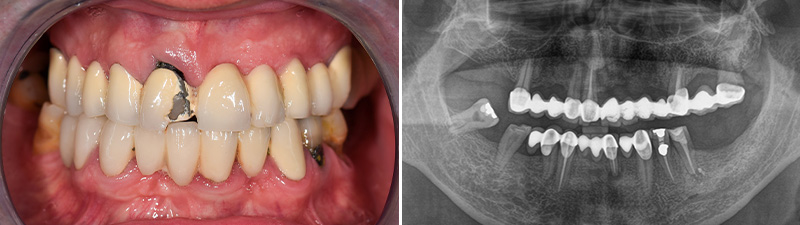

Un patient de 60 ans se présente pour un examen et une consultation en vue d’une réhabilitation prothétique du maxillaire supérieur. L’examen clinique et une radiographie panoramique révèlent un ancien bridge métal-céramique, des dents avec de profondes poches parodontales, et des caries sur les dents piliers. Plusieurs options thérapeutiques sont proposées. Il opte pour une réhabilitation implantaire par la méthode « All-on-4 ».

Fig. 01 : patient avant la réhabilitation implantaire par la méthode « All-on-4 ».

Nous utilisons des photographies intra et extra-orales, un CBCT, ainsi que des empreintes numériques des deux arcades en occlusion pour l’analyse préopératoire. En l’absence de contre-indications, et après avoir confirmé la qualité et quantité osseuse suffisantes, nous procédons à l’intervention.

Fig. 02 : photographie intraorale préopératoire et radiographie panoramique préopératoire.